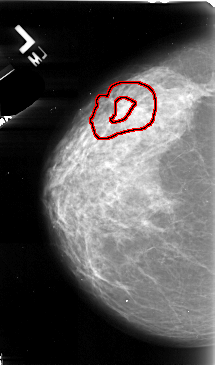

A_1078_1.LEFT_MLO

LEFT_MLO LINES 5491 PIXELS_PER_LINE 3421 BITS_PER_PIXEL 16 RESOLUTION 42 OVERLAY

FILE: A_1078_1.LEFT_MLO.OVERLAY

TOTAL_ABNORMALITIES 1

ABNORMALITY 1

LESION_TYPE MASS SHAPE ARCHITECTURAL_DISTORTION MARGINS SPICULATED

ASSESSMENT 5

SUBTLETY 2

PATHOLOGY MALIGNANT

TOTAL_OUTLINES 1

BOUNDARY